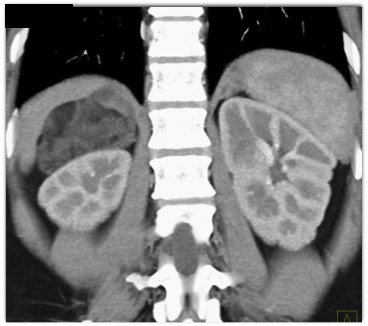

The best diagnosis in this case of an incidental adrenal mass is?

adrenal adenoma

adrenal myelolipoma

pheochromocytoma

indeterminate lesion